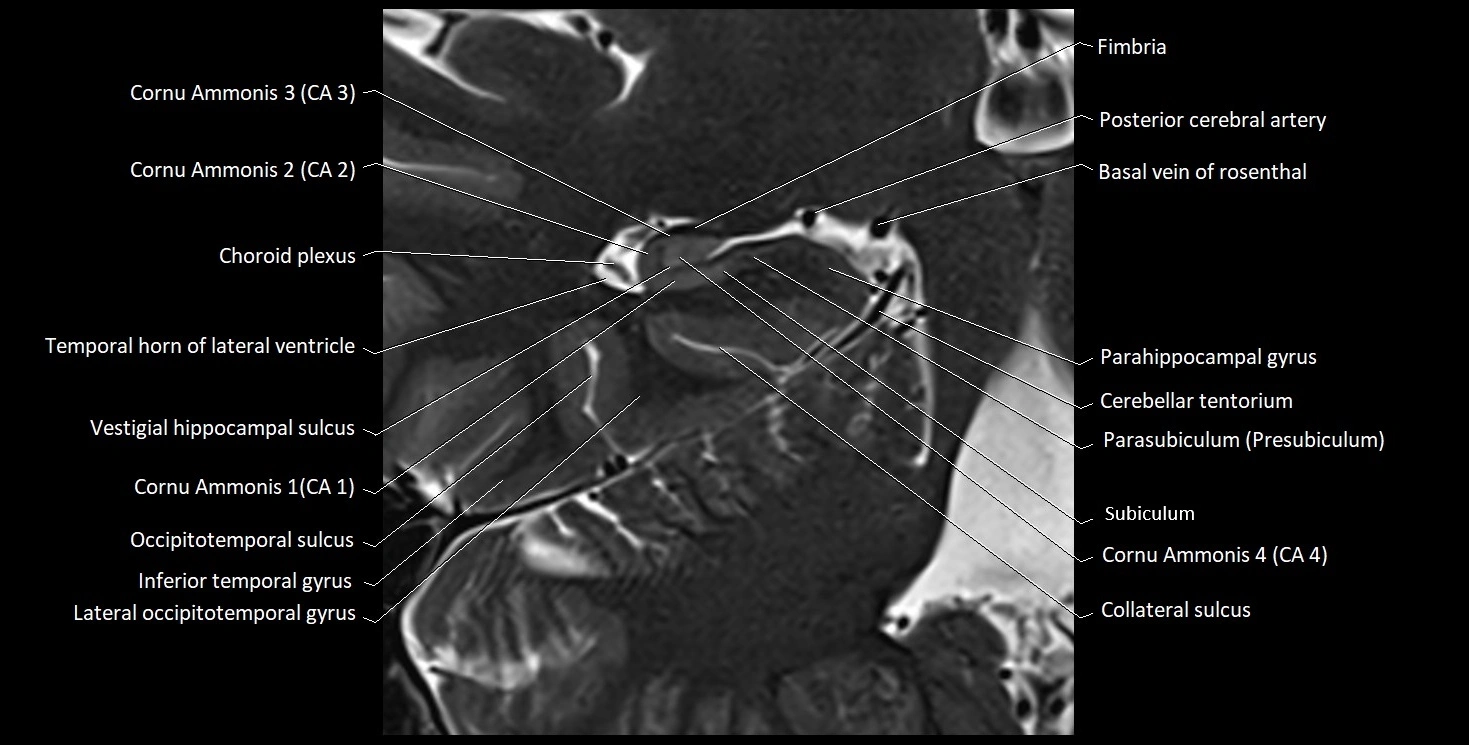

MRI images

image